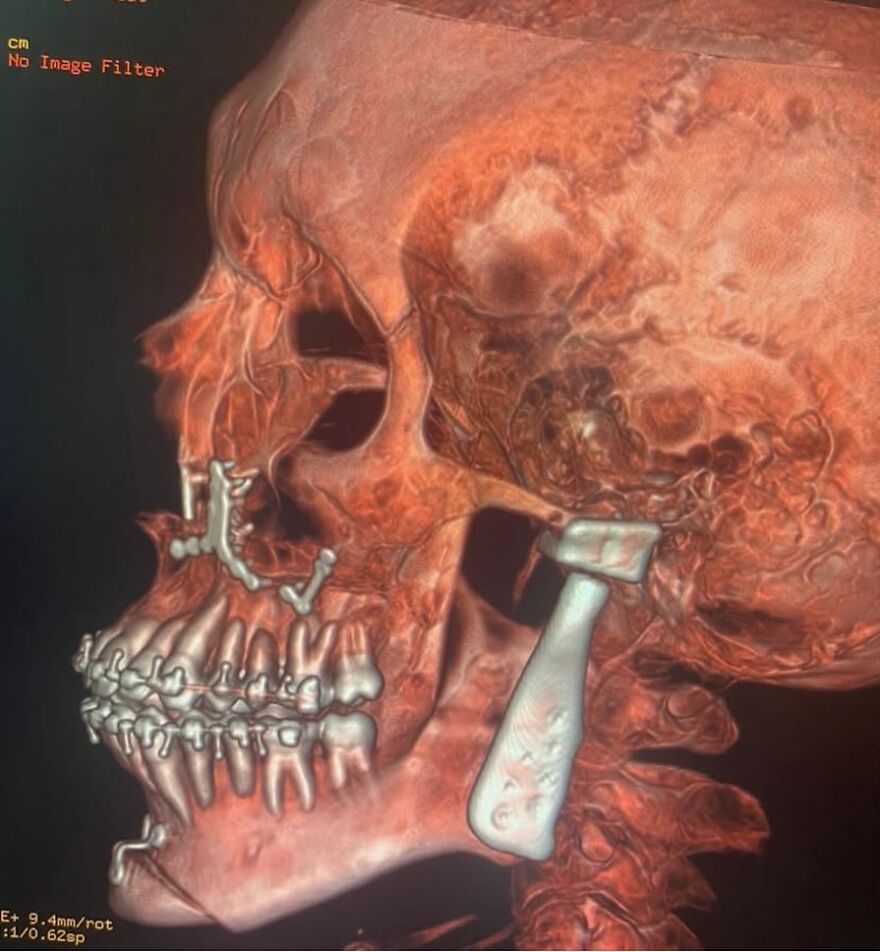

Anterior cervical discectomy and fusion

“Anterior cervical discectomy and fusion (ACDF) is a surgery to remove a herniated or degenerative disc in the neck. An incision is made in the throat area to reach and remove the disc. A graft is inserted to fuse together the bones above and below the disc.“